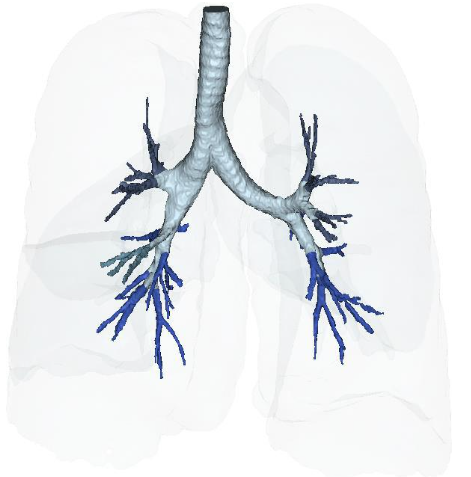

Figure 15A: Vascular Perfusion of Lungs Post-treatment IV deployment at 6 months. Figure 15B: Post IV deployment cSVF therapy in Long COVID-19 clinical trial NCT04326036 at 6 months. NOTE: Improved perfusion, throughout, but particularly in the lower distal lung. Figure 16: Restoration of the near terminal Tracheobronchial tree, pre-treatment showing blunting and loss of distal bronchiolar tree. Figure 16B: Post-treatment IV cSVF with elongation of distal bronchiolar tree at six months. NOTE: With this post-treatment changes with cSVF was an accompanying reduction in airway resistance and pressures within the lung parenchyma. Higher pressures in pre-treatment image were located in the Upper lobes (less efficient and higher pressures in pre-treatment), whereas the shift from upper to lower lung parenchyma accompanied Improve vascular supply and perfusion, and patients no longer experienced difficulties in inhalation capabilities.